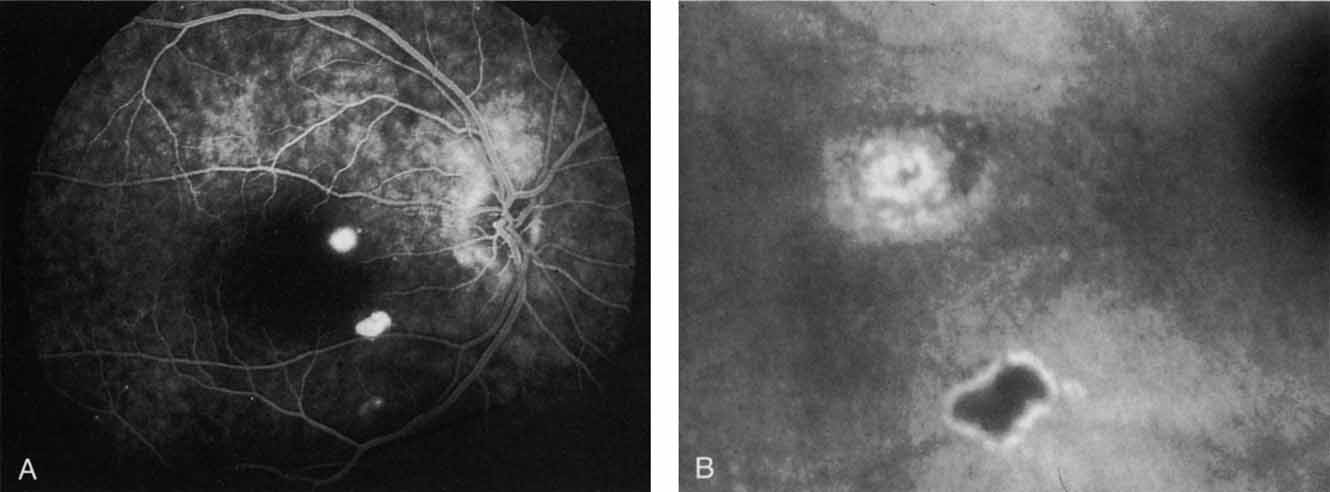

Most promising in this category of inflammatory choroidopathies is a better detection and understanding of the lesions of multifocal choroiditis. Multiple large, scattered, hypofluorescent spots are seen on ICG angiography, particularly in the later phases of the angiogram69 (Fig. 18). These lesions are not evident either on clinical examination or on fluorescein angiography. In addition to having these larger hypofluorescent lesions, patients with multifocal choroiditis have smaller dot-like lesions and hyperfluorescent foci that do not correlate with lesions seen clinically or by FA. They involve the posterior pole and in some patients extend into the mid-periphery. There is also a “papillotropic” involvement, with confluent hypofluorescent lesions surrounding the optic nerve,69 which may be useful in understanding the associated blind-spot enlargement evident in this condition.70 Other zonal visual field defects have been associated with this condition,70 and corresponding ICG abnormalities have been documented in some patients.69

Fig. 18 A. Clinical photograph of a patient with active inflammation associated with multifocal choroiditis. An atrophic scar from previous laser photocoagulation treatment is noted in the temporal macula. The patient reported visual disturbance, and an enlarged blind spot was noted on visual field testing. B. Late-phase indocyanine green study demonstrating a multitude of hypofluorescent spots that were larger than those seen with multiple evanescent white dot syndrome and more numerous and more extensively distributed than appreciated on clinical examination. Note that there is marked confluence of these lesions around the optic nerve, which may help to explain the enlarged blind spot noted on visual field testing.

Natural history data indicate that with progressive increase in vitritis and associated choroidal inflammation, an increase in the number and extent of these hypofluorescent lesions can be documented.40 Furthermore, use of oral steroid therapy as a means of controlling this inflammatory process has been documented to produce not only clinical resolution of the inflammatory process but also corresponding resolution of the hypofluorescent lesions seen on ICG angiography.69 These clearly demonstrated lesions not only may lead to a better understanding of the process of inflammation involved in multifocal choroiditis and potential management strategies but also may serve to differentiate this condition from the ocular histoplasmosis syndrome.

In contrast to multifocal choroiditis, ocular histoplasmosis syndrome does not demonstrate any large, hypofluorescent lesions on the ICG angiographic examination.69 Instead, there are frequently mid- and late-phase hyperfluorescent lesions in the posterior pole in areas that appear normal both clinically and on fluorescein angiography (Fig. 19). These hyperfluorescent lesions may represent sites of subclinical choroidal inflammation. The presence of these lesions on ICG angiography not only may serve to distinguish the histoplasmosis syndrome but also may serve to explain the apparent de novo appearance of new atrophic spots and CNV in what was previously presumed to be normal chorioretinal tissue.

Fig. 19 A. Clinical photograph of a patient with recurrent choroidal neovascularization associated with ocular histoplasmosis syndrome. A few focal “histo spots” are noted in the superior macula. B. Late-phase indocyanine green study demonstrating hyperfluorescence in the central macula corresponding to recurrent neovascularization. Multiple intensely hyperfluorescent dots are noted throughout the macular region, which do not correspond to any detectable lesion noted clinically or via fluorescein angiography. These focal spots may represent sites of subclinical inflammation at the level of the choroid.